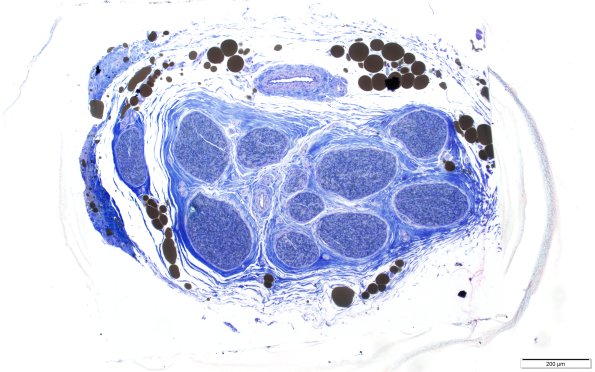

Washington University Experience | PERIPHERAL NEUROPATHY | 1 NORMAL NERVE ANATOMY | 6 Infant Peripheral Nerve | 1A1 Normal Sural nerve, 3 mo age (Case 1) Plastic 10X scale bar

A whole mount image with a scale bar is consistent with a ~1 mm sized nerve measured along its greatest axis. (Toluidine blue stained one micron thick plastic embedded section)